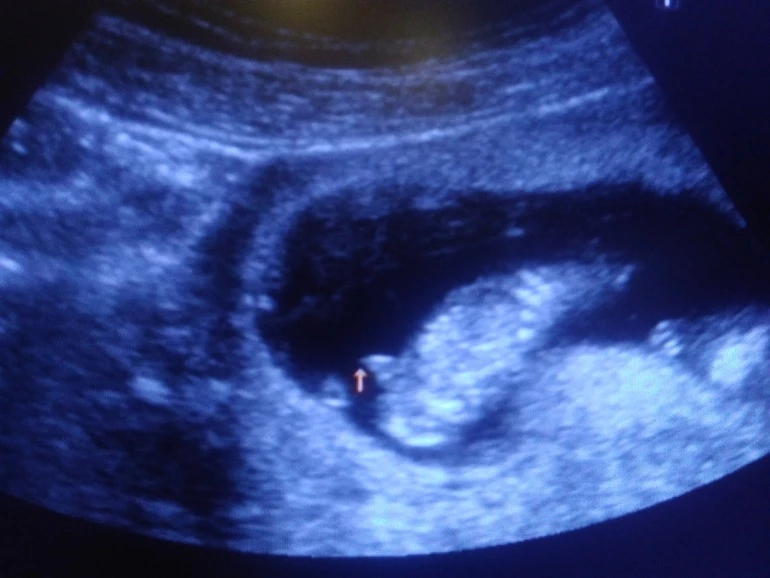

Активный такой мальчуган, еле рассмотрели все! Сказала врач, что редко такое бывает в 12 недель, но "причандал" серьезный, сказала, что сомнений нет-пацан, и показала со всех сторон папину радость))) лежит на спине, пинается ногами и сосёт палец.

Ну вот и позади первый скрининг 12+3, познакомился папа с пузожителем, все хорошо и закрашиваю значок- у нас мальчик!!! Ах, как папа счастлив, и слышать не хотел, что может быть девочка. По ходу сын услышал его мольбы и отрастил в первую очередь "началко", а теперь будет равномерно от "началка" расти))))))))) Почему началко?!- это муж мой так говорит, мол это у него не конец, а началко, он от него вверх и вниз равномерный)))))))))))))) Активный такой мальчуган, еле рассмотрели все! Сказала врач, что редко такое бывает в 12 недель, но "причандал" серьезный, сказала, что сомнений нет-пацан, и показала со всех сторон папину радость))) лежит на спине, пинается ногами и сосёт палец. Я конечно не знаю, что бы там не говорили за кишечник, но я со вчерашнего дня слышу возню именно в одном месте, уровень широкой резинки леггинсов, именно очень похоже на шевелюшки. Ну вот так и получилось, как я предполагала с самых первых дней, - будет мальчик - это они такие капризные))) не успела // увидеть, а уже кипишу сколько пережила, что в 7 недель казалось, что я уже недель 20 беременная, нервотреп казявоШный ))))))). Но все самое интересное ещё только впереди. А вот и папина гордость